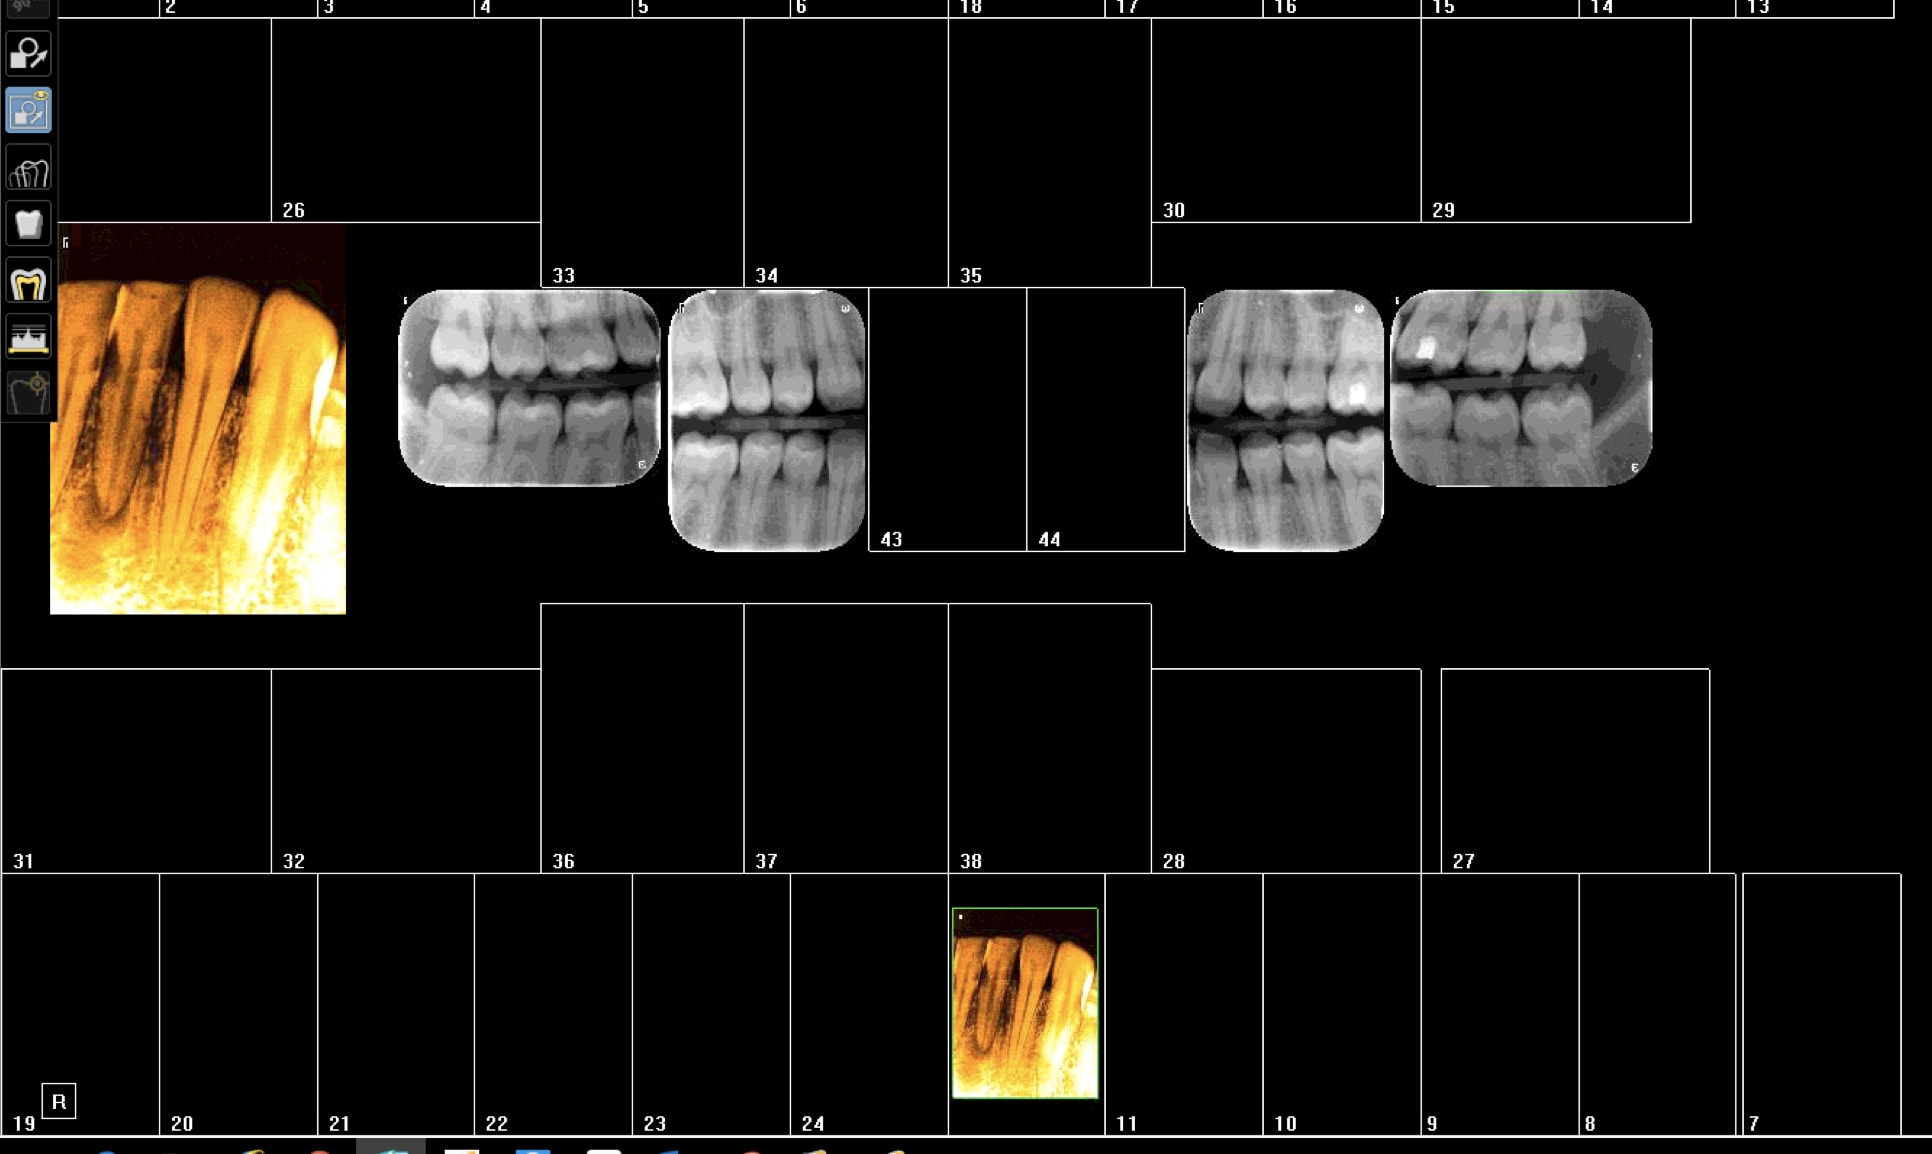

Non mais moi je ne cote que rarement des consults. Nouvelle patiente douleur 31. Signe d'appel donc pano ? -))))

Capture d écran 2018 07 09 09.17 - Eugenol

Franchement trop pourries ces plaques on dirait un pano. -)))

Je déconne c'est team viewer qui merde. -)))